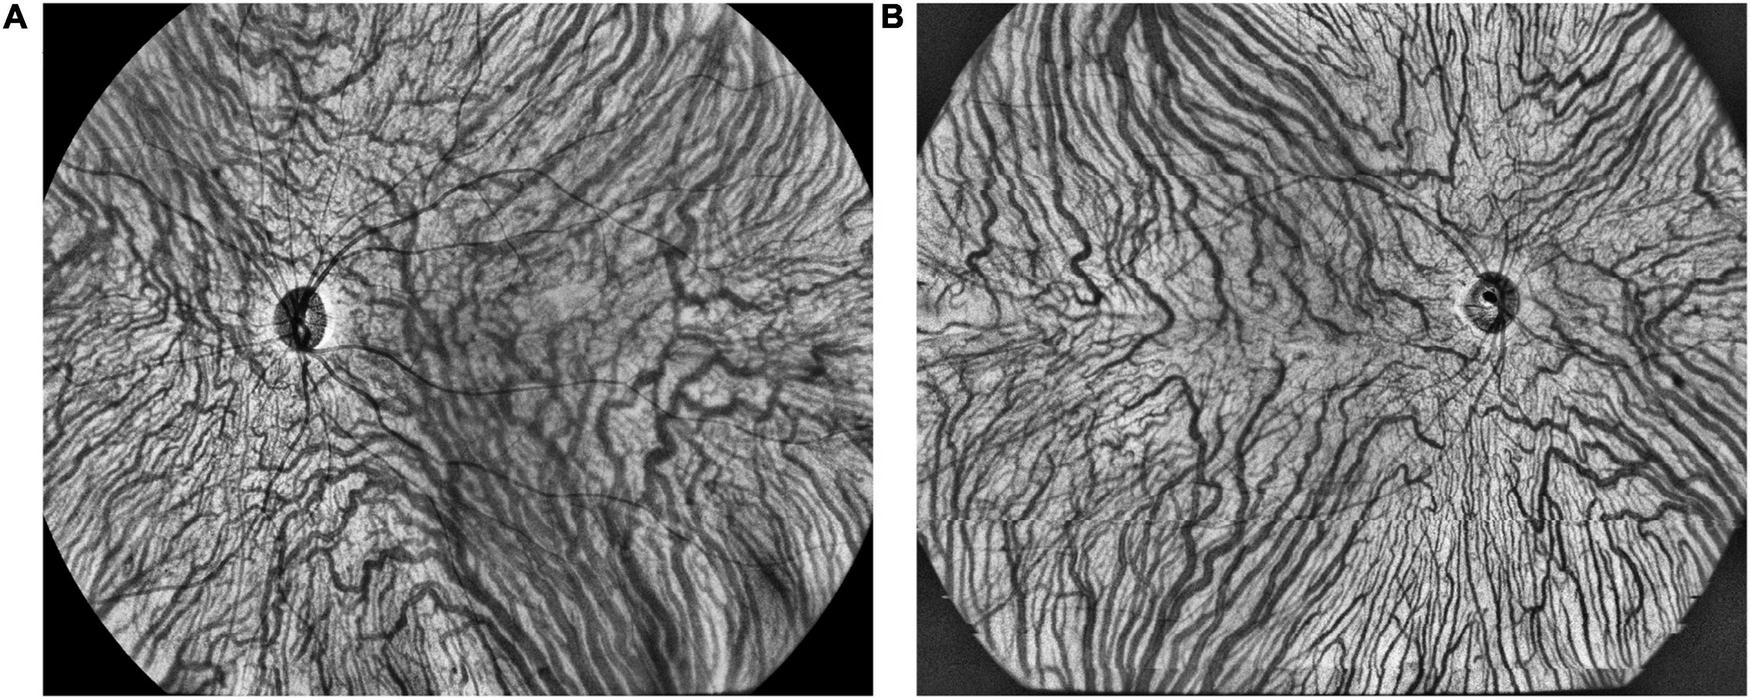

FIGURE 5

The representative vortex vein anastomoses in a CSC eye (A) and symmetric vortex vein in a healthy eye (B) on en face large choroidal vessel layer.

The presence of anastomosis between superior and inferior vortex veins was demonstrated using en face OCT and ICGA. The presence of dilated vortex veins, choroidal vascular hyperpermeability, and anatomical and functional anastomoses between the superior and inferior vortex veins were judged and confirmed by the two experienced retinal experts (YYO and ZMW). On en face large choroidal vessel layer of OCT images, anastomoses in CSC were always presented as asymmetric dilated vortex veins in the posterior pole, lost horizontal watershed between the superior and inferior vortex veins (22, 23). The proportions of vortex vein anastomoses were compared among the CSC, fellow and control eyes, as well as their corresponding CVI in the central regions.

The representative vortex vein anastomose in a CSC eye and its control in a healthy eye were presented in Figure 5. There were 25 (78.1%), 15 (46.9%), and 5 (15.3%) eyes with vortex vein anastomoses in CSC, fellow and control eyes (P < 0.001). As shown in Table 4, in all the three groups, the average central CVI in eyes with anastomoses was significantly higher than those without anastomoses (in the group of CSC eyes: 42.8 ± 5.1% vs. 38.4 ± 2.7%, P = 0.039; in the group of fellow eyes: 43.3 ± 2.8% vs. 36.1 ± 5.1%, P < 0.001; in the control group: 42.8 ± 3.1% vs. 37.0 ± 5.5%, P = 0.031; respectively).